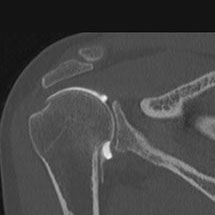

Cet examen consiste à injecter à l’aide d’une aiguille, sous guidage radiologique un produit de contraste iodé à l’intérieur d’une articulation. Les articulations concernées sont variées : genou, cheville, épaule, coude, poignet, hanche.

L’arthrographie est généralement immédiatement complétée par un scanner de l’articulation (arthroscanner). Ceci ne nécessitera pas de deuxième piqûre.

L’arthrographie, généralement couplée à l’arthroscanner permet au radiologue d’établir un diagnostic précis sur l’état des cartilages de l’articulation concernée, de déceler des ruptures partielles ou complètes des tendons, des ligaments, ou encore de déceler des corps étrangers au sein des articulations explorées. Cette exploration peut être couplée à une infiltration dans le même temps opératoire.